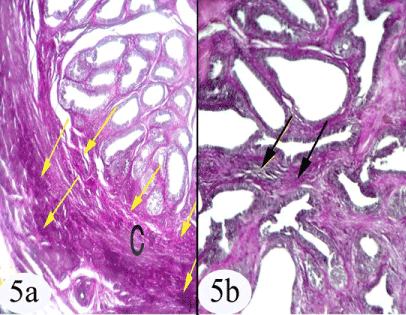

| Figure 5: a) A photomicrograph of the immature seminal gland showing the distribution of the elastic fibers in the capsule (arrow), capsule (C). b) Showing the distribution of elastic fibers in the inter-acinar connective tissue stroma (arrow). Stain: a,b) Weigert's elastic a) Obj. x4: Oc.x10 b) Obj. x10: Oc.x10 |